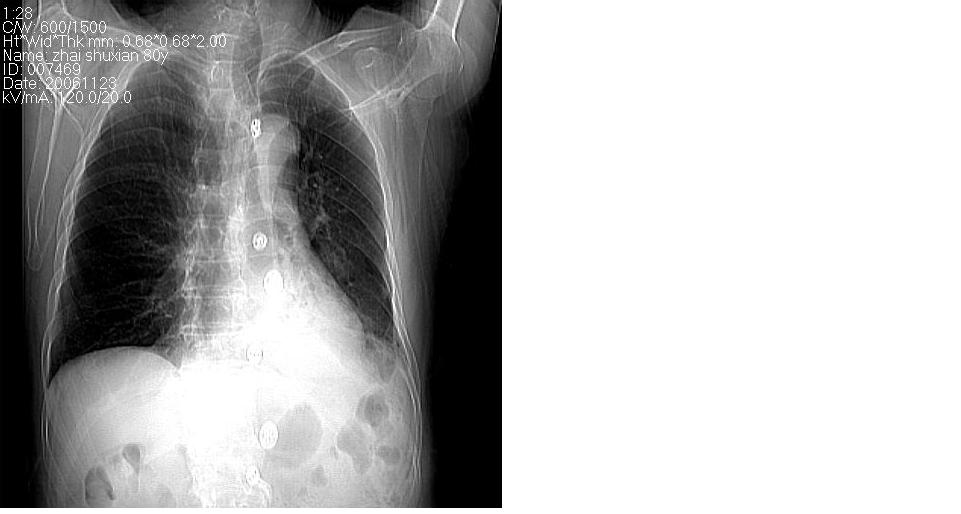

男 80岁,外院病人,有脑梗塞病史,近两个月发热,体温38.5度左右,抗炎后体温正常,药物停有发热。

左肺下叶略萎陷、实变,内可见含气支气管征。左舌叶、中叶亦见少许斑片状高密度区,边界不清。纵隔未见肿大淋巴结影。

左下肺体积缩小,密度增高,见片增密影。边界模糊,见支气管充气像,肺门纵隔无异示,心脏气管左移,左侧胸腔少量积液。考虑肺部感染伴部分肺不张[有脑梗塞病史坠积性肺炎可能]

左下肺体积缩小,密度增高,并见大片状致密影,边界模糊,其内见支气管充气像,肺门纵隔无异常,心脏气管左移,左侧胸腔少量积液。考虑:左肺炎性病变伴不张。